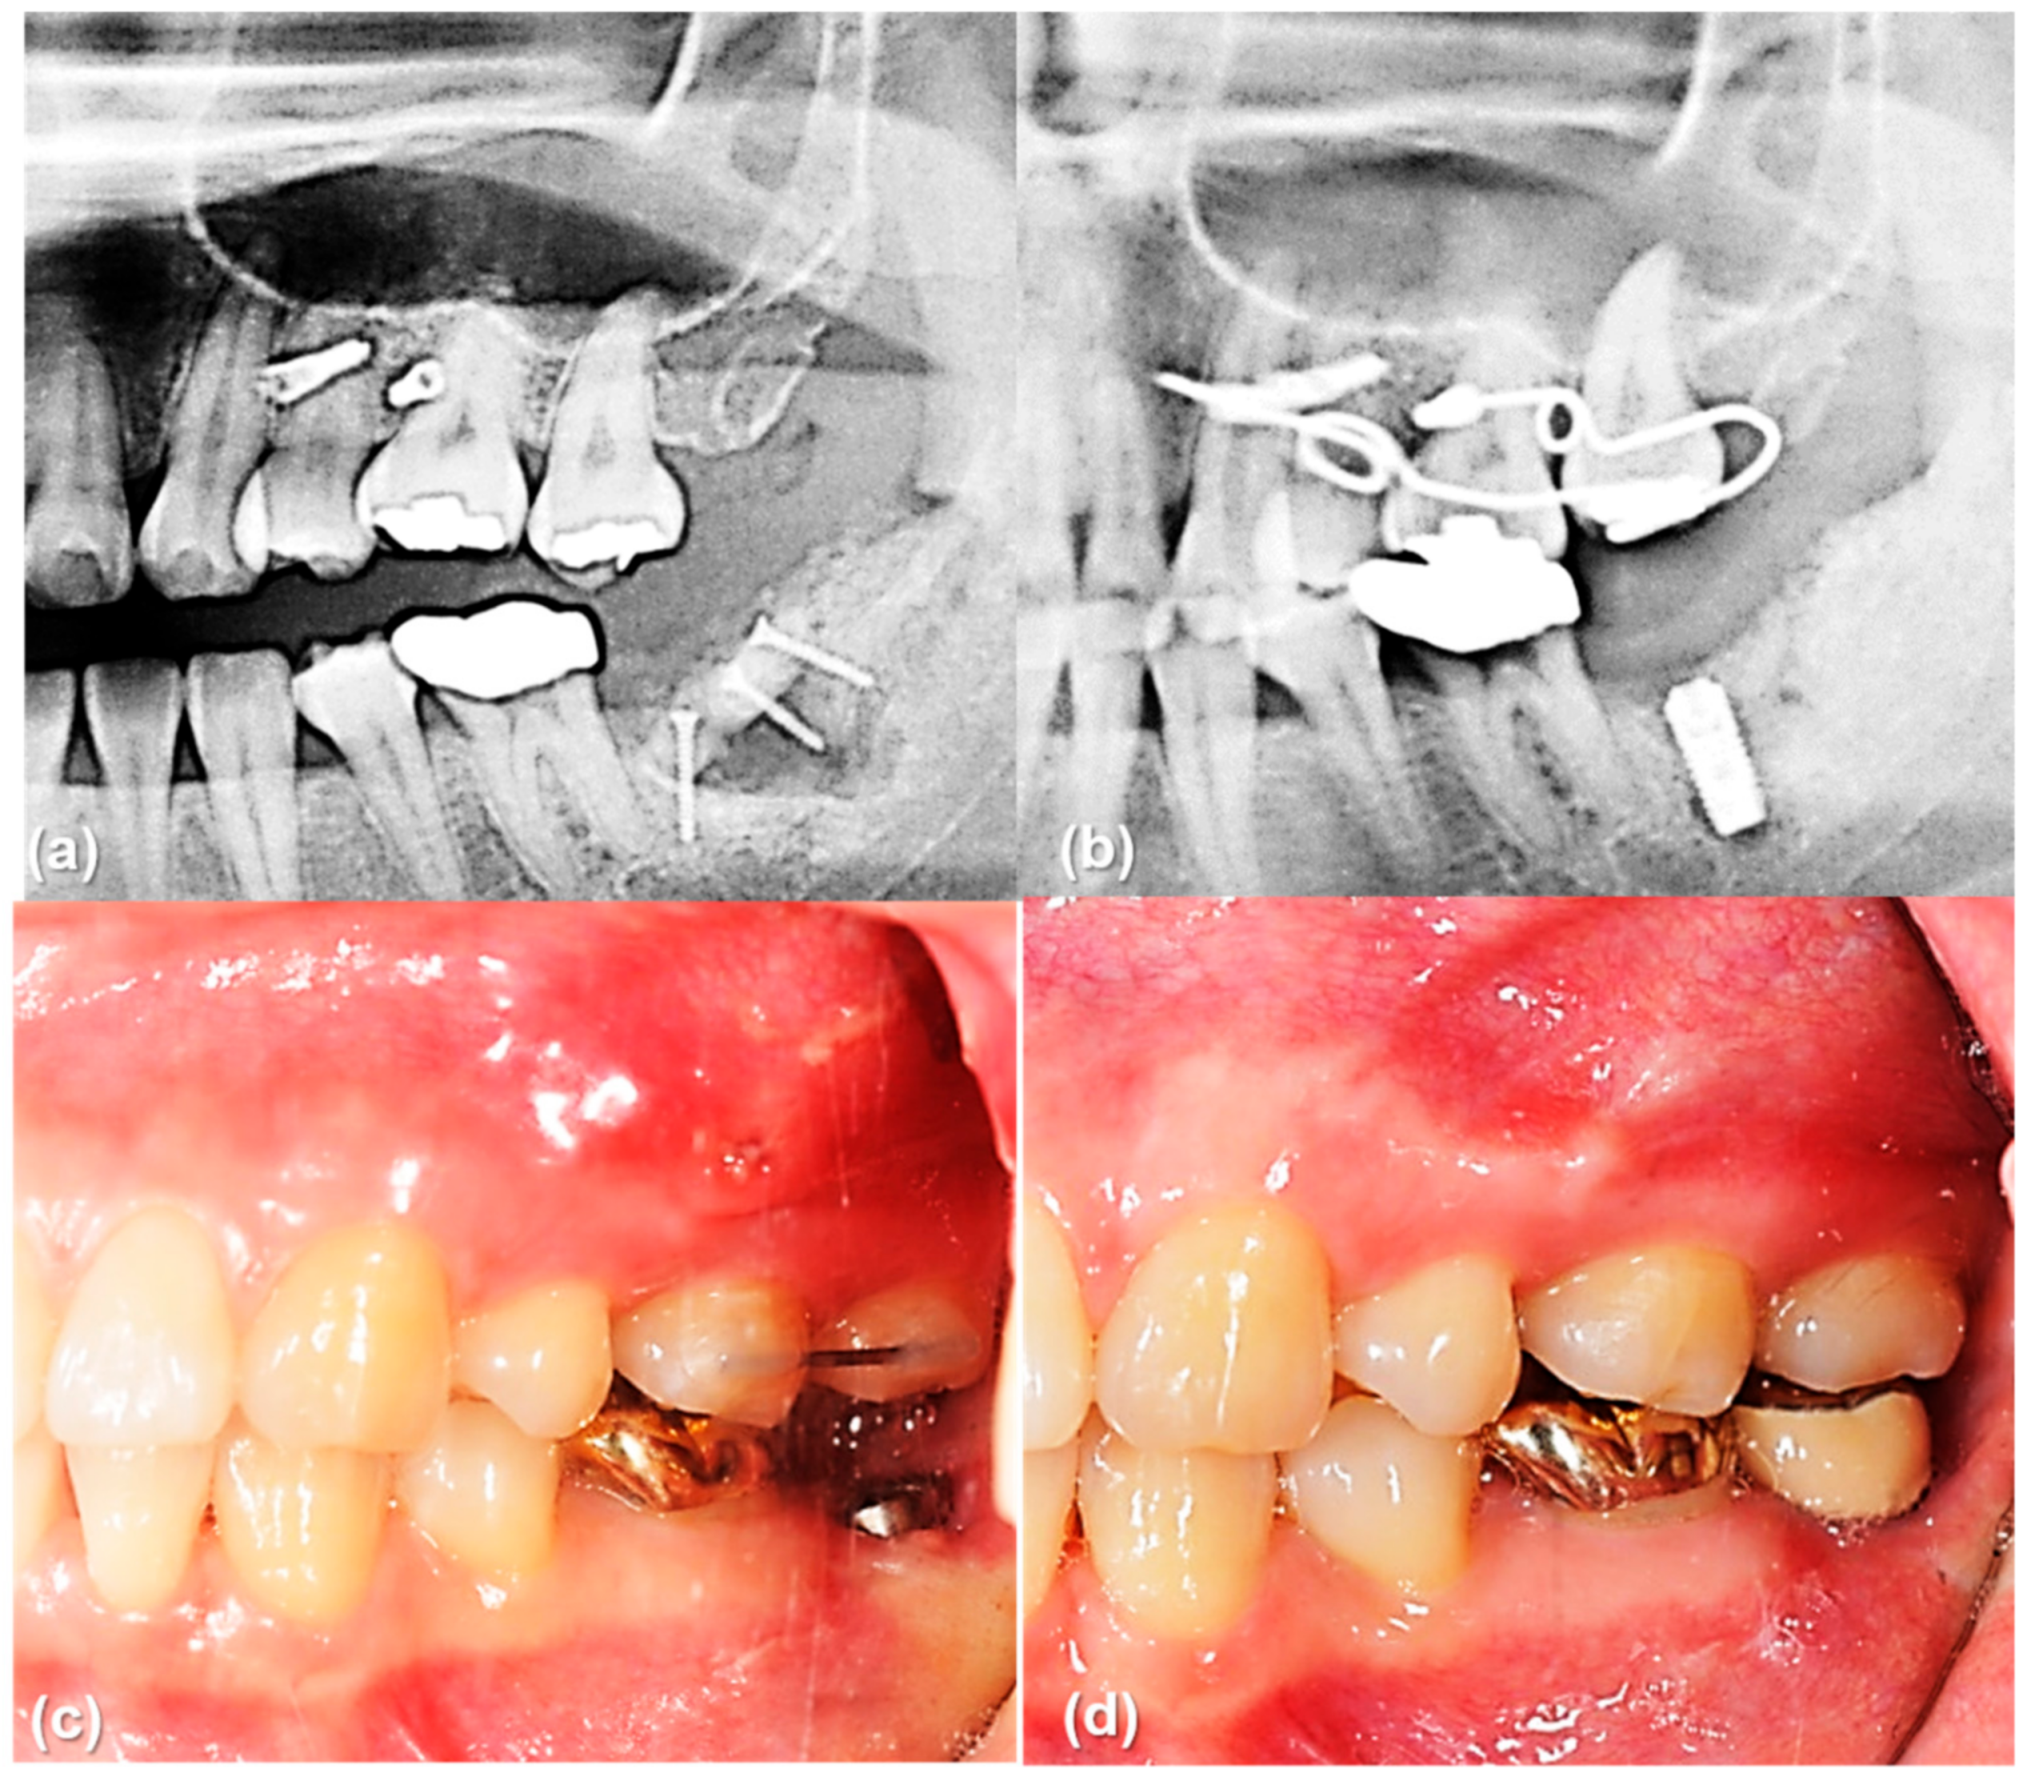

The main result of this study that the rotational resistance of the orthodontic miniscrew with a novel design was increased would be applied to the clinical situation where the increased moment is required. Figure 9 and Figure 10 shows an example of the counterclockwise rotational force applied to an orthodontic miniscrew. A patient with an extruded upper left second molar was treated by one of the authors (K.R.C). The patient agreed and signed an informed consent form that the authors would use photos for the publication of an article. In this case, the orthodontic wire used to intrude the extruded upper left second molar was inserted into a hole in the heads of both orthodontic miniscrews between the upper left second premolar and the upper left first molar on the buccal and palatal side of alveolar bone. On the buccal side, the wire generated a counterclockwise rotational moment on the orthodontic miniscrew. If the amount of moment had been higher than the rotational resistance of the orthodontic miniscrew, the orthodontic miniscrew would have been loosened and the intrusion of the upper left second molar would have failed. In this case, the osseointegration was effective enough to stabilize the orthodontic miniscrew under the heavy moment of the counter-clockwise rotation.

Figure 9.

The orthodontic miniscrew supported the counterclockwise rotational force in a patient with extruded upper left second molar: (a) The patient has an extruded upper left second molar (*), especially the palatal cusp. To intrude this tooth, two orthodontic miniscrews (1.8 mm in diameter, 8.5 mm in length SLA surface treated mini-implant, C-implant, CIMPLANT co., Seoul, Korea) were inserted on the buccal and palatal sides between upper left second premolar and upper left first molar. A spring was designed to apply an intruding force (black dotted arrow) on the palatal cusp of the second molar, with its wire was passing through the holes of the orthodontic miniscrews. The spring generates a counterclockwise rotational moment on the buccal orthodontic miniscrew (yellow dotted arrow); (b) Six months later, the upper left second molar was intruded successfully. Both orthodontic miniscrews stayed stable in spite of the rotational moments.